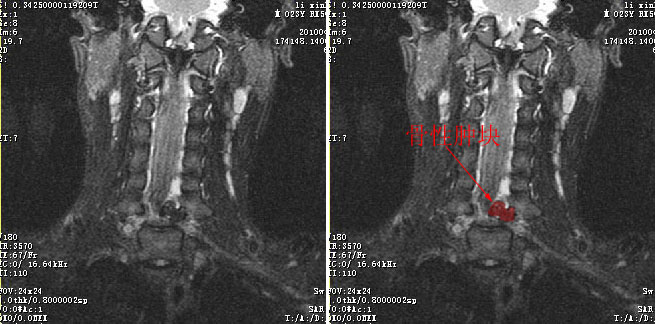

标题: MRI2838:椎管内占位,请讨论性质(CT+mri)

男24岁因一年来感头昏,查体四肢肌力及感觉无异常。颈椎dr未见异常,mri发现c7水平段椎管内左侧占位。患者于7年前有车祸伤病史(但是未检查,自述无异常)。请讨论是否是机化血肿或骨折片,能除外是肿瘤?

标题: 考虑骨软骨瘤可能性大

椎管内骨性肿块,与第7颈椎左下关节突关系密切,向椎管内生长,第7颈椎椎体左后缘受压变形,边缘可见硬化边,与肿块间间隙清晰。mri扫描肿块内可见骨髓信号,考虑骨软骨瘤可能性大。